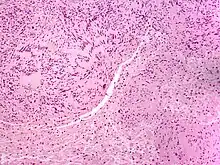

| Solitary circumscribed neuroma | |

A neuroma (/njʊəˈroʊmə/; plural: neuromata or neuromas) is a growth or tumor of nerve tissue.[1] Neuromas tend to be benign (i.e. not cancerous); many nerve tumors, including those that are commonly malignant, are nowadays referred to by other terms.

Neuromas can arise from different types of nervous tissue, including the nerve fibers and their myelin sheath, as in the case of genuine neoplasms (growths) like ganglioneuromas and neurinomas.

The term is also used to refer to any swelling of a nerve, even in the absence of abnormal cell growth. In particular, traumatic neuroma results from trauma to a nerve, often during a surgical procedure. Morton's neuroma affects the foot. Neuromas can be painful, or sometimes, as in the case of acoustic neuromas, can give rise to other symptoms.